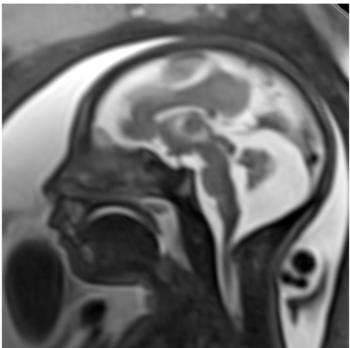

Figure 6. Images obtained in the case of a 24-year-old woman pregnant with twins, with characteristic rash at 9 weeks of pregnancy and confirmed Zika virus infection. (For each pair of images, the first image is of twin A, and the second image is of twin B.) At 14 weeks of gestational age, the fetal head size of both twins was normal. The head size never went below the 3rd percentile for either fetus in examinations at 19–28 weeks. (a, b) Sagittal and (c, d) axial fetal MR images were obtained at 36 weeks. (e, f) Axial and (g, h) surface reconstruction postnatal CT images and (i, j) axial T2-weighted and (k, l) coronal MR images were obtained 1 week after delivery at 38 weeks of gestational age. There is severe microcephaly with profound frontal lobe hypoplasia. Calcifications in the subcortical white matter at the gray matter–white matter junction are visualized. Both twins have a flattened appearance of the pons. The spinal cord is atrophic (best seen on a). Redundant skin is seen in the occipital region. There is polymicrogyria involving the frontal and parietal regions and atrophic cortex and white matter in the occipital regions. Each twin has hypoplasia of the corpus callosum, with prominent fornices. There is abnormal myelination in the occipital region that, in twin A (i), has the appearance of a cyst or septation within the ventricle. The cerebellum is somewhat small and nodular. There is lack of rotation of the hippocampi.

High-res (TIF) version